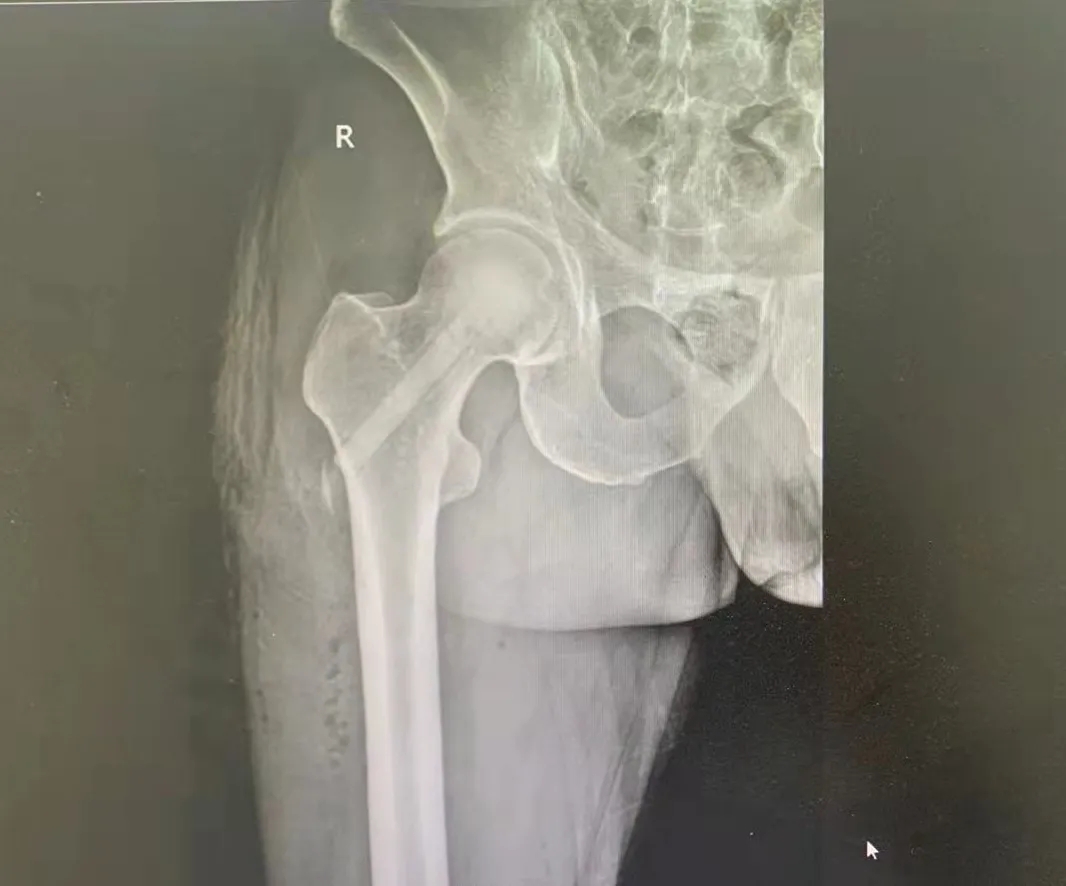

52岁的孟先生两月前无明显诱因出现右髋部疼痛,站立及行走时加重,休息后可缓解,呈缓慢加重趋势。11月中旬曾于当地医院检查示“双侧股骨头坏死”,未做治疗。后情况愈发严重,蹲起时疼痛明显,站立时间缩短,不可远距离行走,经朋友介绍后急来华润医疗徐州市矿山医院就诊。

入院后,MRI示:双侧股骨头缺血性坏死,右侧股骨头局部骨髓水肿。确诊为双侧股骨头无菌性坏死(Ficat—II期)。骨科专业技术主任李先启、骨二科副主任顾署光及其团队经过研究及讨论,并与家属协商后决定进行保头治疗,手术后既可以避免人工关节置换,而取得一劳永逸的长期效果。

术前影像